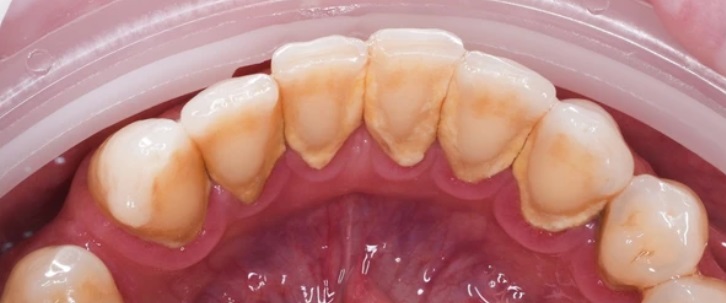

Проблема

У пациента выраженные зубные отложения и пигментированный налёт, особенно в области нижних и верхних передних зубов, с воспалённым краем десны.

Решение

Проведена профессиональная гигиена полости рта — налёт и камень удалены, зубы стали заметно чище и светлее, состояние десны улучшилось.